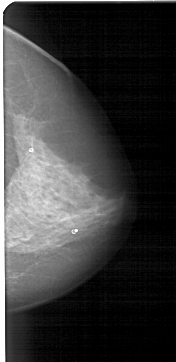

A_1316_1.LEFT_CC

LEFT_CC LINES 4726 PIXELS_PER_LINE 2641 BITS_PER_PIXEL 12 RESOLUTION 43.5 OVERLAY